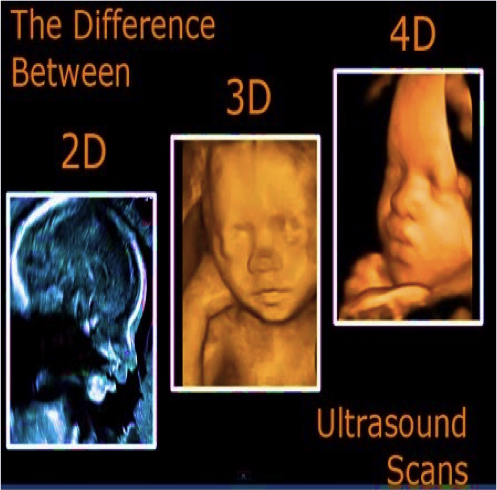

Sebenarnya Apakah Bedanya Usg 2d 3d Dan 4d Simak Berikut Ini Moms

Sebenarnya Apakah Bedanya Usg 2d 3d Dan 4d Simak Berikut Ini Moms

Perbedaan Usg 4 Dimensi Dengan Versi 2d Dan 3d Intip Potret Serta Penjelasannya Moms Semua Halaman Nakita

Perbedaan Usg 4 Dimensi Dengan Versi 2d Dan 3d Intip Potret Serta Penjelasannya Moms Semua Halaman Nakita

Perbedaan Usg 2 3 Dan 4 Dimensi

Perbedaan Usg 2 3 Dan 4 Dimensi

Perbedaan Usg 4 Dimensi Dengan Versi 2d Dan 3d Intip Potret Serta Penjelasannya Moms Semua Halaman Nakita

Perbedaan Usg 4 Dimensi Dengan Versi 2d Dan 3d Intip Potret Serta Penjelasannya Moms Semua Halaman Nakita

Perbedaan Usg 4 Dimensi Dengan Versi 2d Dan 3d Intip Potret Serta Penjelasannya Moms Semua Halaman Nakita

Perbedaan Usg 4 Dimensi Dengan Versi 2d Dan 3d Intip Potret Serta Penjelasannya Moms Semua Halaman Nakita

Perbedaan Usg 2 3 Dan 4 Dimensi

Perbedaan Usg 2 3 Dan 4 Dimensi

Perbedaan Usg 4 Dimensi Dengan Versi 2d Dan 3d Intip Potret Serta Penjelasannya Moms Semua Halaman Nakita

Perbedaan Usg 4 Dimensi Dengan Versi 2d Dan 3d Intip Potret Serta Penjelasannya Moms Semua Halaman Nakita